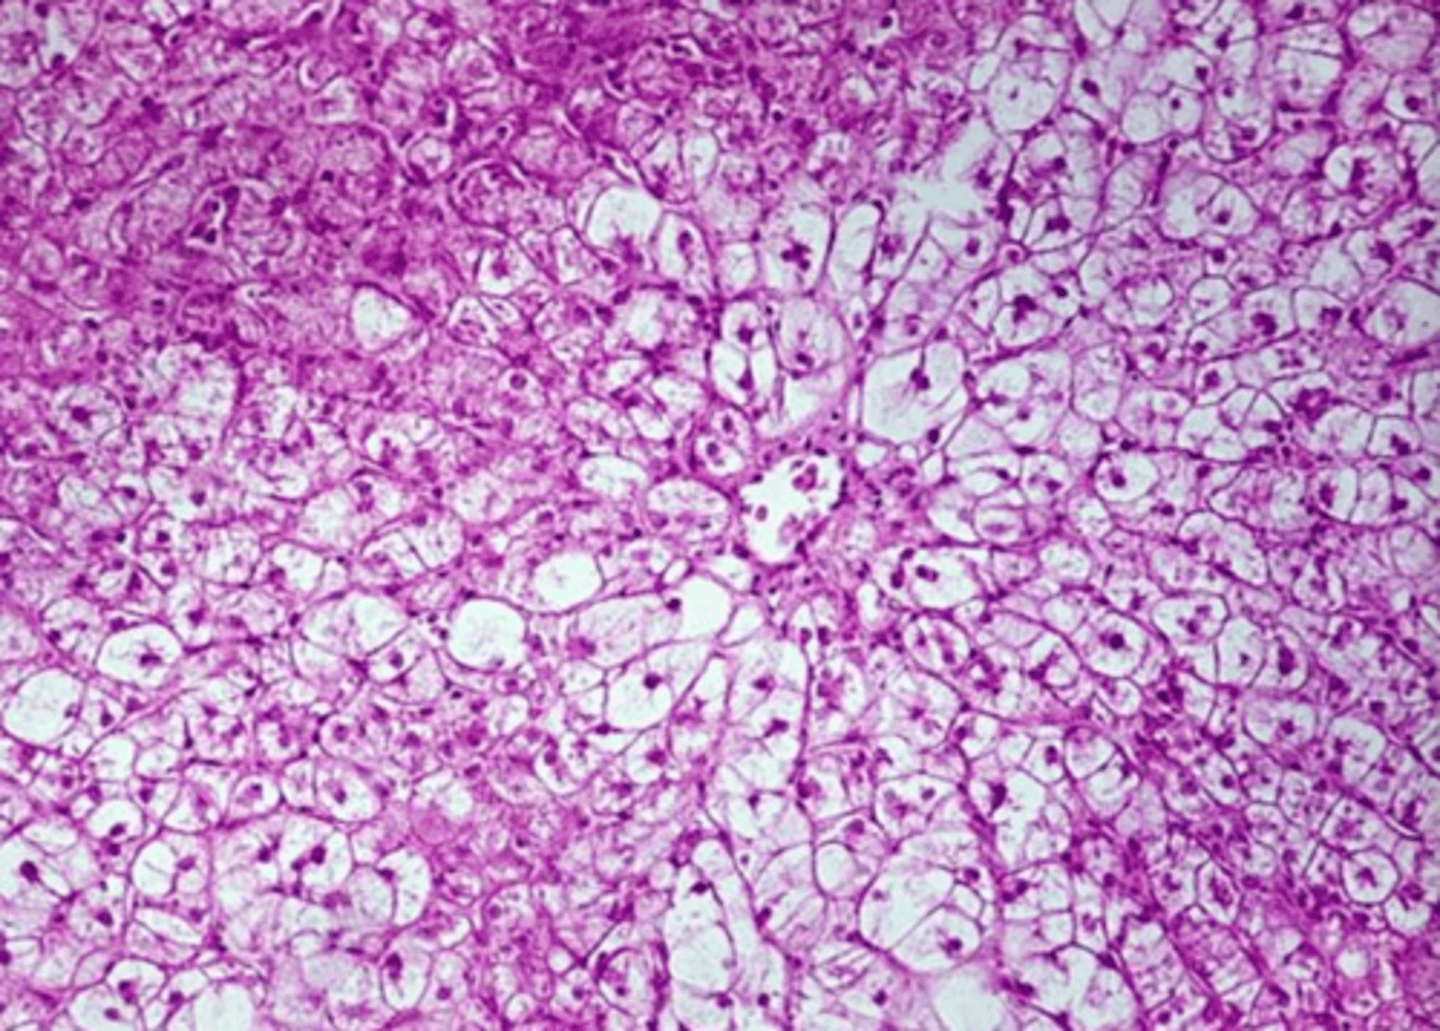

macrovesicular lipidosis

Which type of lipidosis is this describing?

Large, clear, sharply defined vacuoles that are larger than the nucleus, distend the

cytoplasm, and displace the nucleus to the periphery of the cell